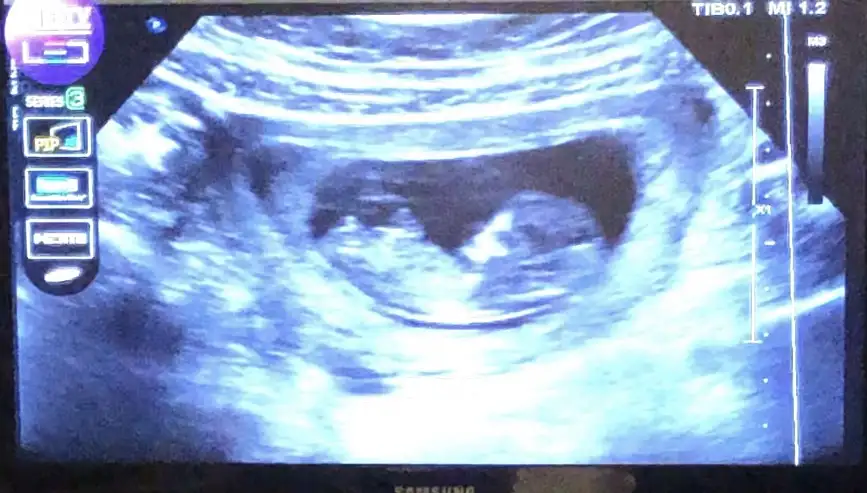

Kızlar dün attım ama kimse yorum yapmadı nub teorisine göre sizce cinsiyet ne? Doktor birşey söylemedi

Eklentiler

• 6855C3AF-A877-47FE-B6B9-1E8B31A0FE74.webp

30,8 KB · Görüntüleme: 68